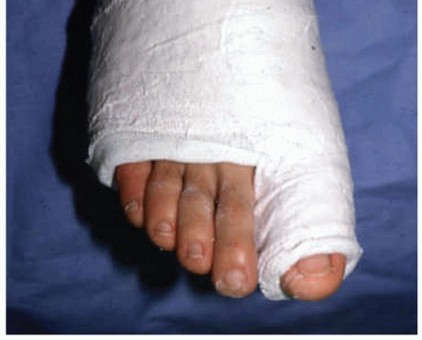

Immobilization with a boot or cast. A toe spica cast with the hallux in plantarflexion relieves tension on the injured plantar complex (FIG 6). Found to be very helpful with a diastased bipartite or fractured sesamoid.

FIG 6 • Plaster toe spica cast for conservative or postoperative care of a turf toe injury.